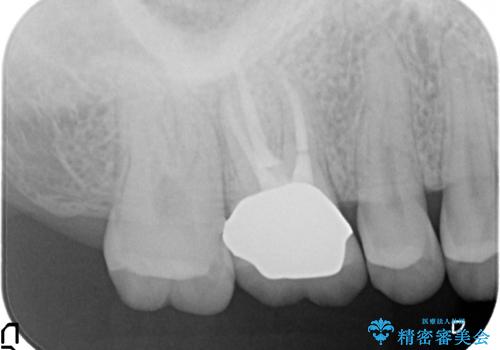

- 見た目が気になるため右上6のゴールドクラウンをセラミックにしたいといらっしゃった方の症例です。

再根管治療を御希望されたため根管治療を行った後、メタルボンドクラウンによる補綴を行いました。

- メタルボンドクラウン(エコノミー)…¥90,000、ファイバーコア…¥20,000、仮歯…¥10,000費用は治療当時の料金となります

金属フレームを用いたメタルボンドクラウンは、オールセラミッククラウンに比べ審美性で劣るというイメージが強いです。しかし歯肉の下までしっかりと被せれば、唇・頬側からは金属部が見えず、十分に審美的です。

また適合もよく、強度も高いので、奥歯の補綴には適したクラウンです。